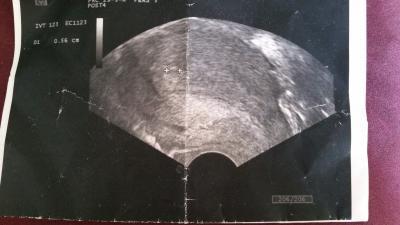

war ja beim FA und sie hat nur eine gaaaaanz kleine Fruchthöhle gesehen,

und nichts drin... bin gespannt muss am 26.7 wieder hin.

Die Fruchthöhle ist 0,56 cm steht da diese beiden Kreuze, Ich hab ja am DI Noch mal Termin , am 26 und ich hoffe das da diesmal mehr zu sehen ist .